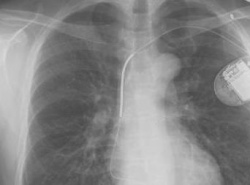

"»ðÀÔÇü Á¦¼¼µ¿±â, Àå±âÀû ºÎÀÛ¿ë À§Çè"

"»ðÀÔÇü Á¦¼¼µ¿±â, Àå±âÀû ºÎÀÛ¿ë À§Çè" (¼¿ï=¿¬ÇÕ´º½º) ÇѼº°£ ±âÀÚ = ½ÉÀå¹Úµ¿ÀÌ °©ÀÛ½º·´°Ô ºÒ±ÔÄ¢ÇØÁú ¶§ À̸¦ °¨Áö, Àü±âÃæ°ÝÀ» °¡ÇÔÀ¸·Î½á ½É¹Úµ¿À» Á¤»óÀ¸·Î ȸº¹½ÃŰ´Â »ðÀÔÇü Á¦¼¼µ¿±â(implanted def...